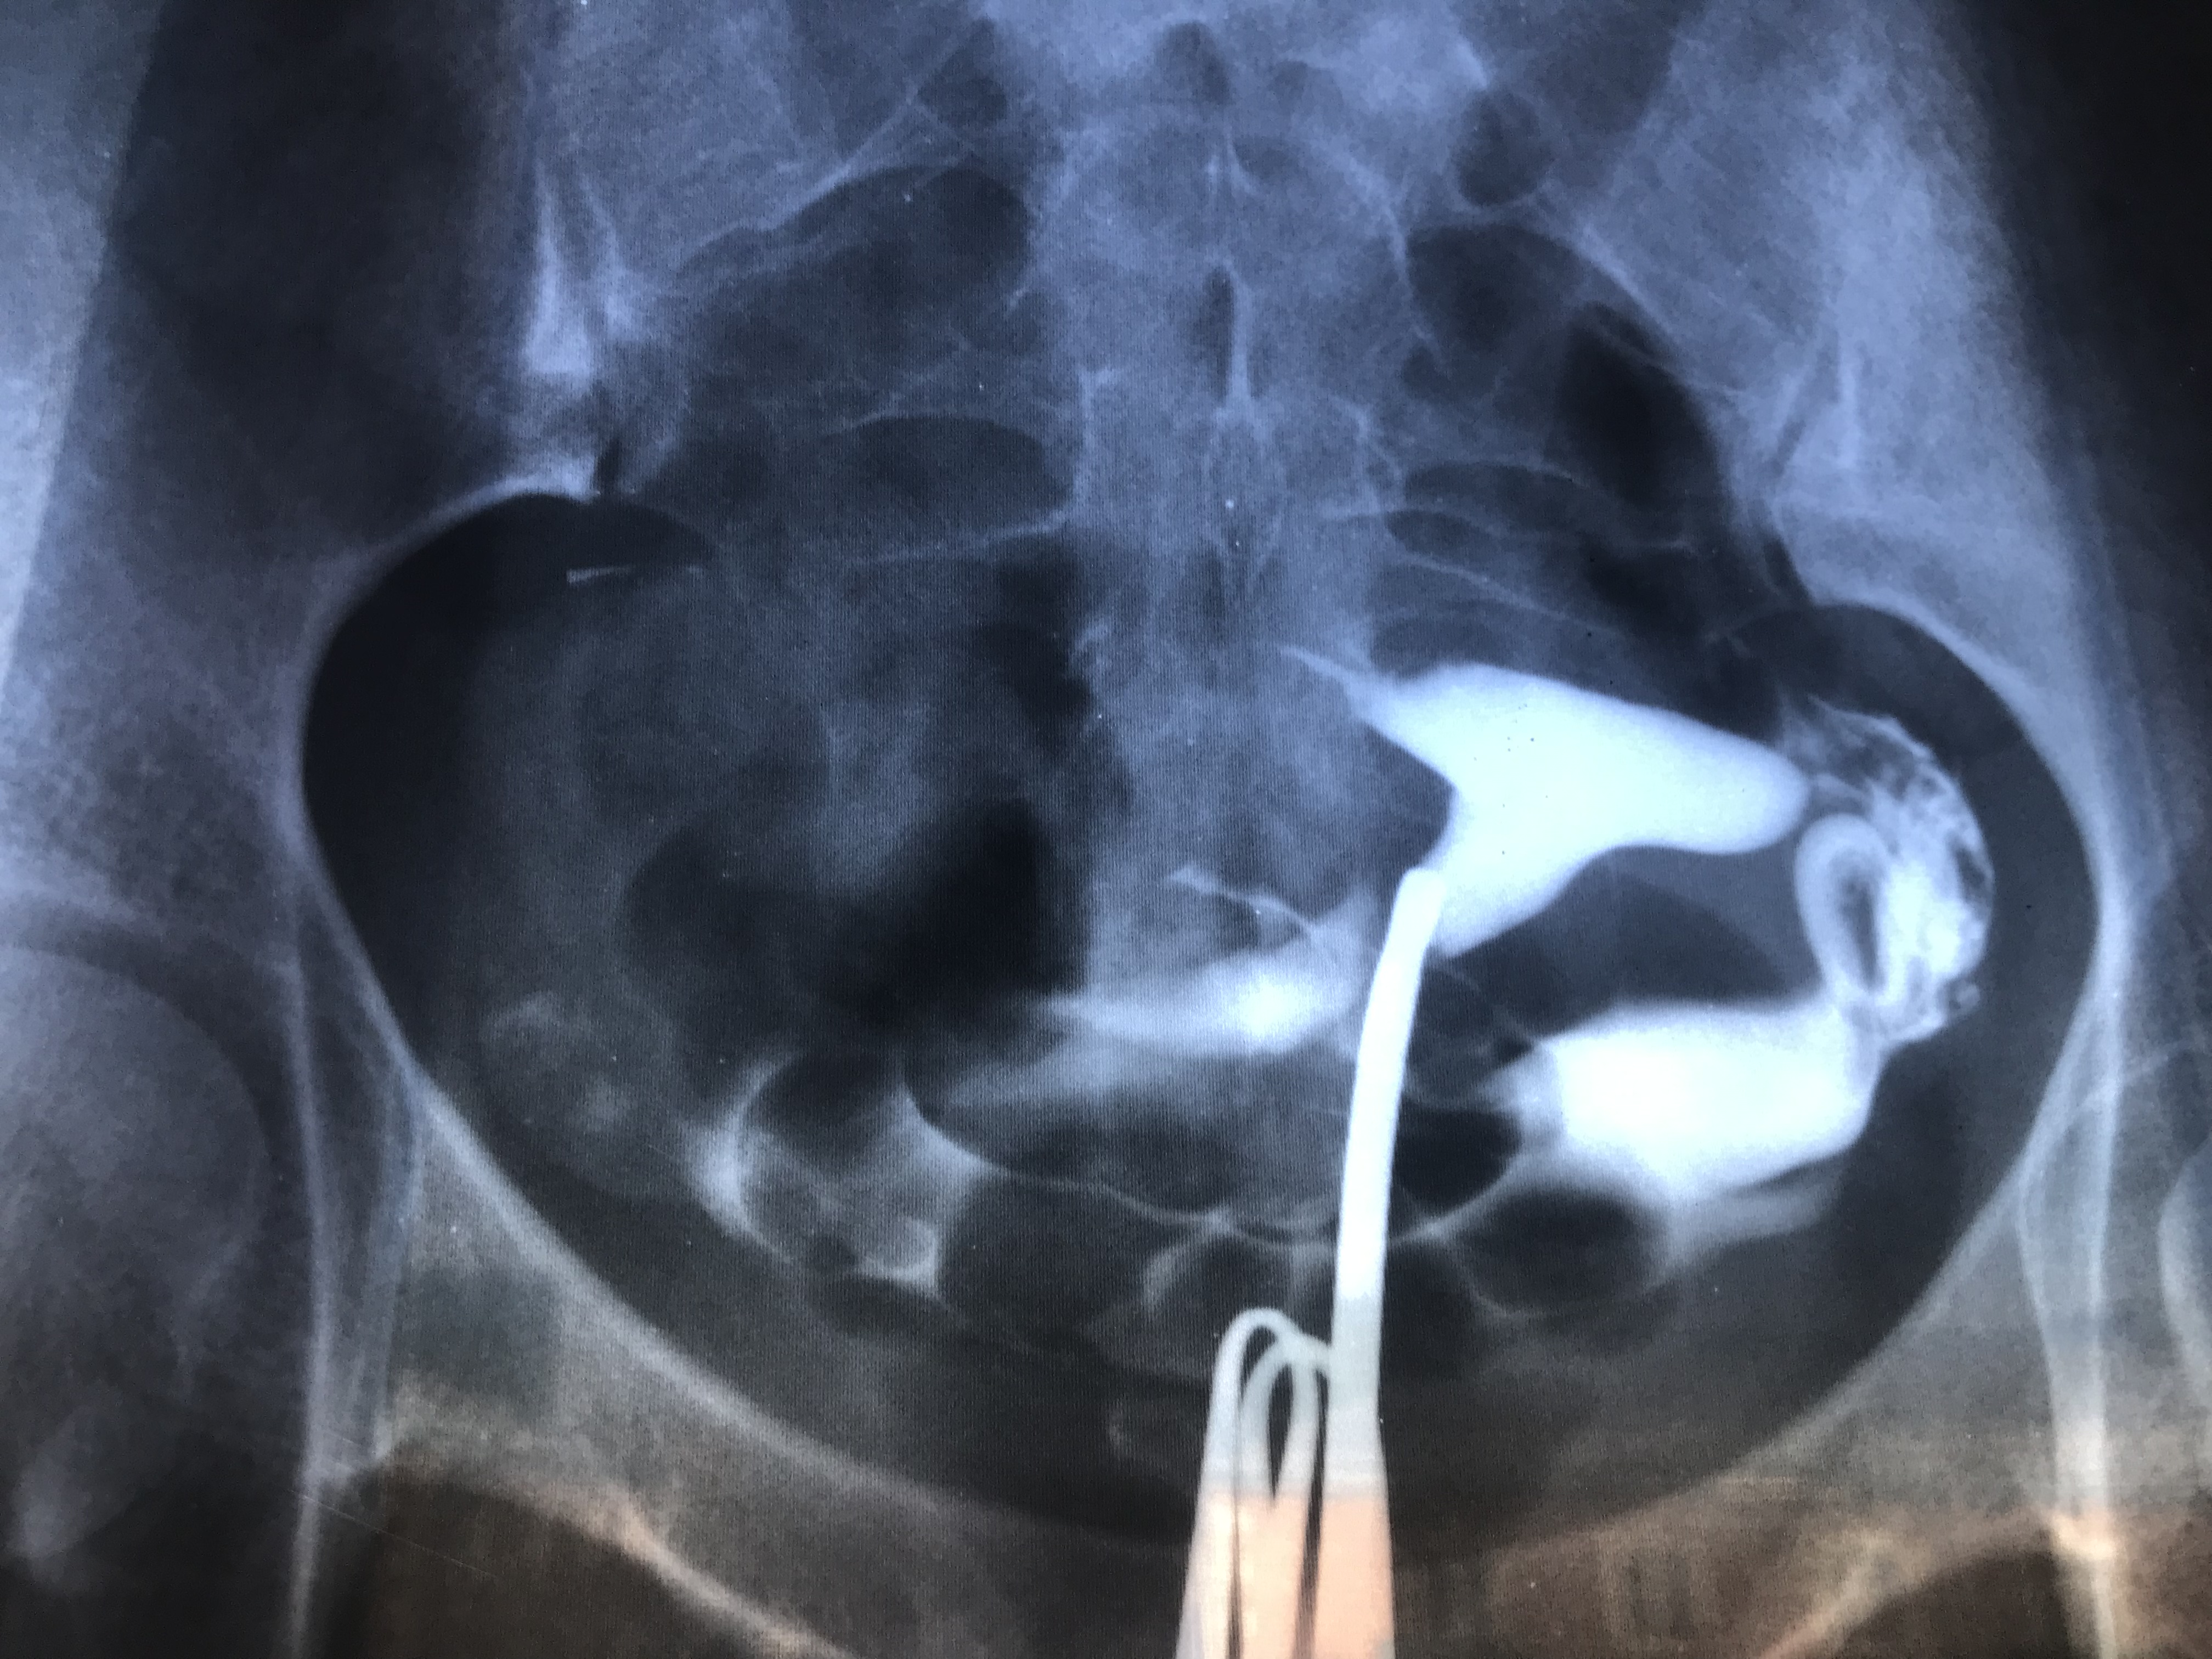

Гистеросальпингография: описание и фотографии